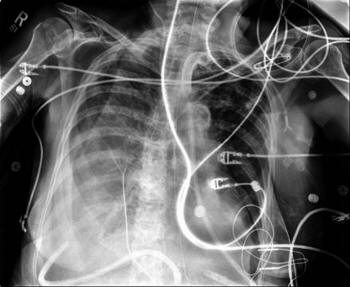

ISSN: 2233-601X (Print) ISSN: 2093-6516 (Online) Thoracic ...

Thoracic Duct Embolization for Chylothorax − 75 − Fig. 1. (A, B) Takayasu’s arteritis and a large aortic aneurysm. (C) After left subclavian artery to left commoncarotid arterial transposition ... Access This Document